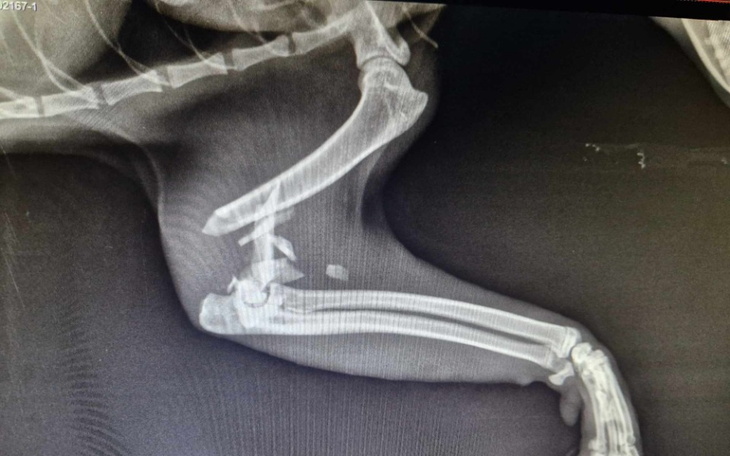

Na szczęście ktoś zareagował i Lord trafił do weterynarza. Już pierwsze oględziny wskazywały na poważne uszkodzenie przedniej łapki. A kolejne badanie potwierdziły poważny uraz. 😢

Zapadła przykra decyzja o amputacji łapki. Ale w przeszłości mieliśmy już kociaki, które straciły łapkę i radziły sobie doskonale. Mamy nadzieję, że i Lord przyzwyczai się do nowej sytuacji. I liczymy na to, że szybko znajdzie kochający, troskliwy domek.